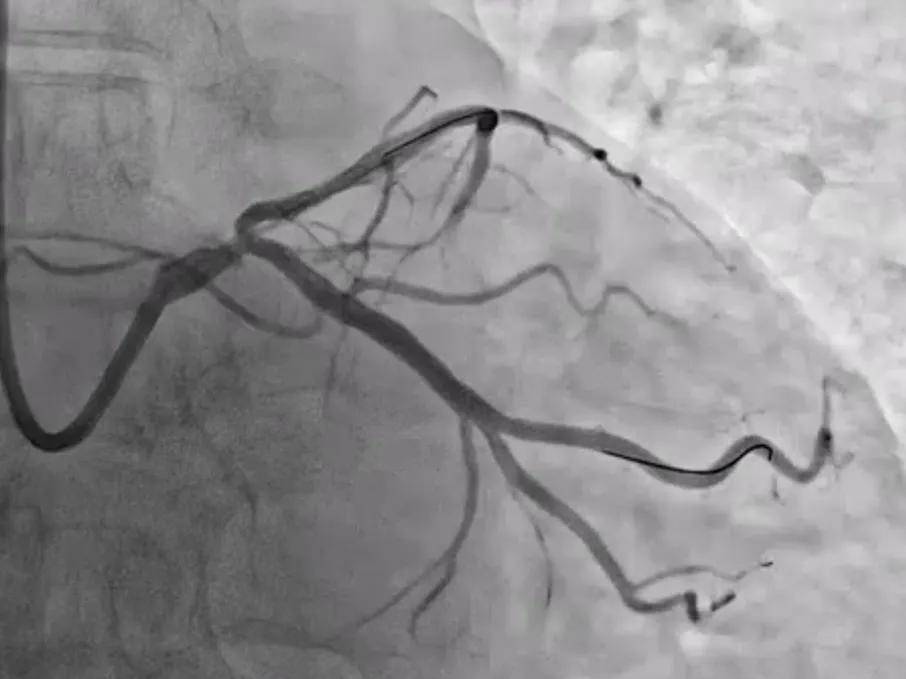

患者为67岁男性,主诉胸闷3月,冠脉CTA及造影均提示左回旋支(LCX)中段重度狭窄,且血管角度较大,传统手动操作难度较高。经全面评估,曾勇主任团队为其制定了个体化治疗方案,决定施行血管介入机器人辅助手术。

图说 / 造影提示LCX中段重度狭窄